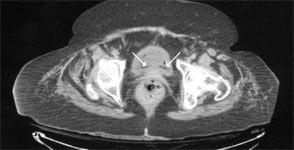

White blood cell count was 9820/μL; blood glucose level, 286 mg/dL; and glycosylated hemoglobin, 7.1%. Urinalysis findings were consistent with urinary tract infection. A CT scan of the abdomen revealed air within the wall of the urinary bladder, compatible with emphysematous cystitis. Because of the patient’s age and comorbidities, she was empirically treated with piperacillin/tazobactam. Blood cultures were negative. Urine culture later grew Escherichia coli.

When intraluminal gas is present, other entities, such as a recent urinary tract instrumentation, trauma, and vesicocolic/vesicovaginal fistulas, should also be considered.2,4,5 Clinical presentations range from no symptoms, descriptive pneumaturia, and irritative voiding symptoms to acute abdomen and severe sepsis.2,3 Thus, a high index of suspicion for emphysematous cystitis is required. The condition is usually diagnosed incidentally by plain abdominal film, ultrasonography, or CT scan findings. Other modalities include direct visualization during cystoscopy or laparotomy and biopsy. 2,3 However, CT remains the preferred diagnostic method, because of its high sensitivity and specificity in detecting gas and the extent and severity of disease and in differentiating other causes of intraluminal gas formation.1,2,5